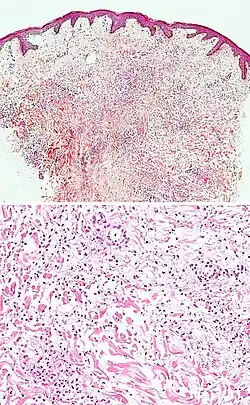

| Kaposi's sarcoma in patch stage | The patch stage typically shows irregular proliferation of jagged vascular channels in the dermis below an integral epidermis. The so-called promontory sign is sometimes found in patch stage lesions and denotes vascular spaces surrounding pre-existing blood (see image).[23]

vessels |